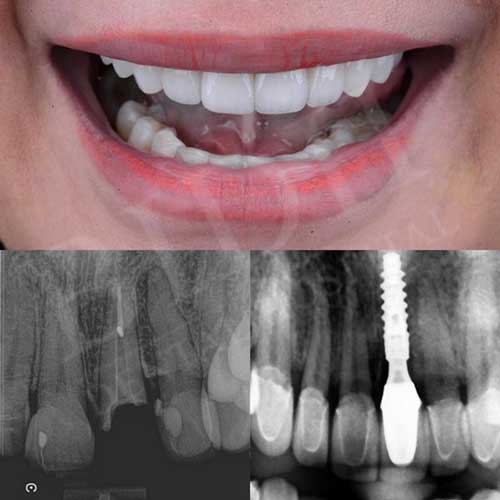

Single Missing Tooth

Single tooth that has been extracted may be replaced with a dental implant crown. Missing tooth should be replaced to prevent bone loss and surrounding teeth from shifting into the gap that can cause crooked teeth will be more complicated to resolve.